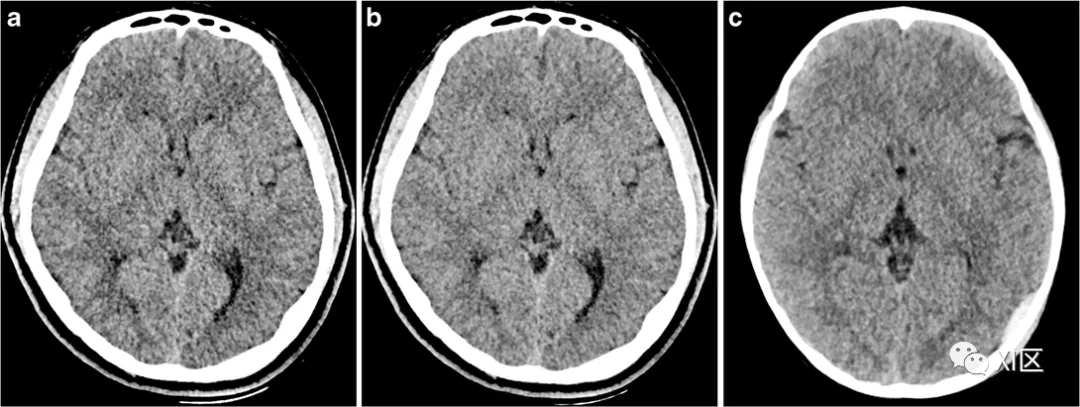

为了更清晰地显示儿童颅脑的灰白质,有学者使用双能量低keV重建来优化。

a–c脑实质图像质量在Mono+、Mono和常规CT中的代表性例子。在一名16岁患有颅面发育不良的男孩中使用60keV(a)的Mono+算法和65keV(b)的Mono算法的虚拟单能成像,在一名14岁男孩中使用常规CT扫描(c),在对难治性癫痫进行有创监测后立即进行术后CT。灰-白质对比噪声比在Mono+组最大(3.45),其次是Mono组(3.05)和常规CT组(2.76),因此显示了使用Mono+对灰质和白质的优越区分。

ParkJ,ChoiYH,CheonJE,edbraincomputedtomographyinchildren:comparisonofimagequalityagainststandardmon,2017:1-11.